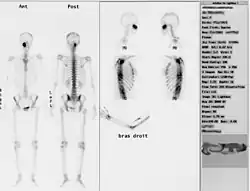

Nuklearne obrazowanie medyczne całego szkieletu. Badanie to wykonuje się gdy:

• podejrzenie nowotworu pierwotnego lub przerzutów do kości, a także ocenę skuteczności terapii,

• zapalenie kości i stawów,

• ocena zmian pourazowych,

• choroby metaboliczne kości.

Stosowany znacznik należy do grupy fosfonianów i jest transportowany za pomocą krwi. Wykazuje on naturalne gromadzenie się w strukturze kostnej – najbardziej intensywnie w kościach dobrze ukrwionych. W stanach chorobowych występuje zwiększenie aktywności procesów metabolicznych – gromadzi się więcej krwi niż w typowych warunkach[9][10]. Obrazowanie w takim przypadku ukazywałoby nadmierne nagromadzenie się znacznika badawczego. Stosuje się przede wszystkim znacznik 99mTc-MDP (metylenodifosfonian) o aktywności 550–750 MBq.